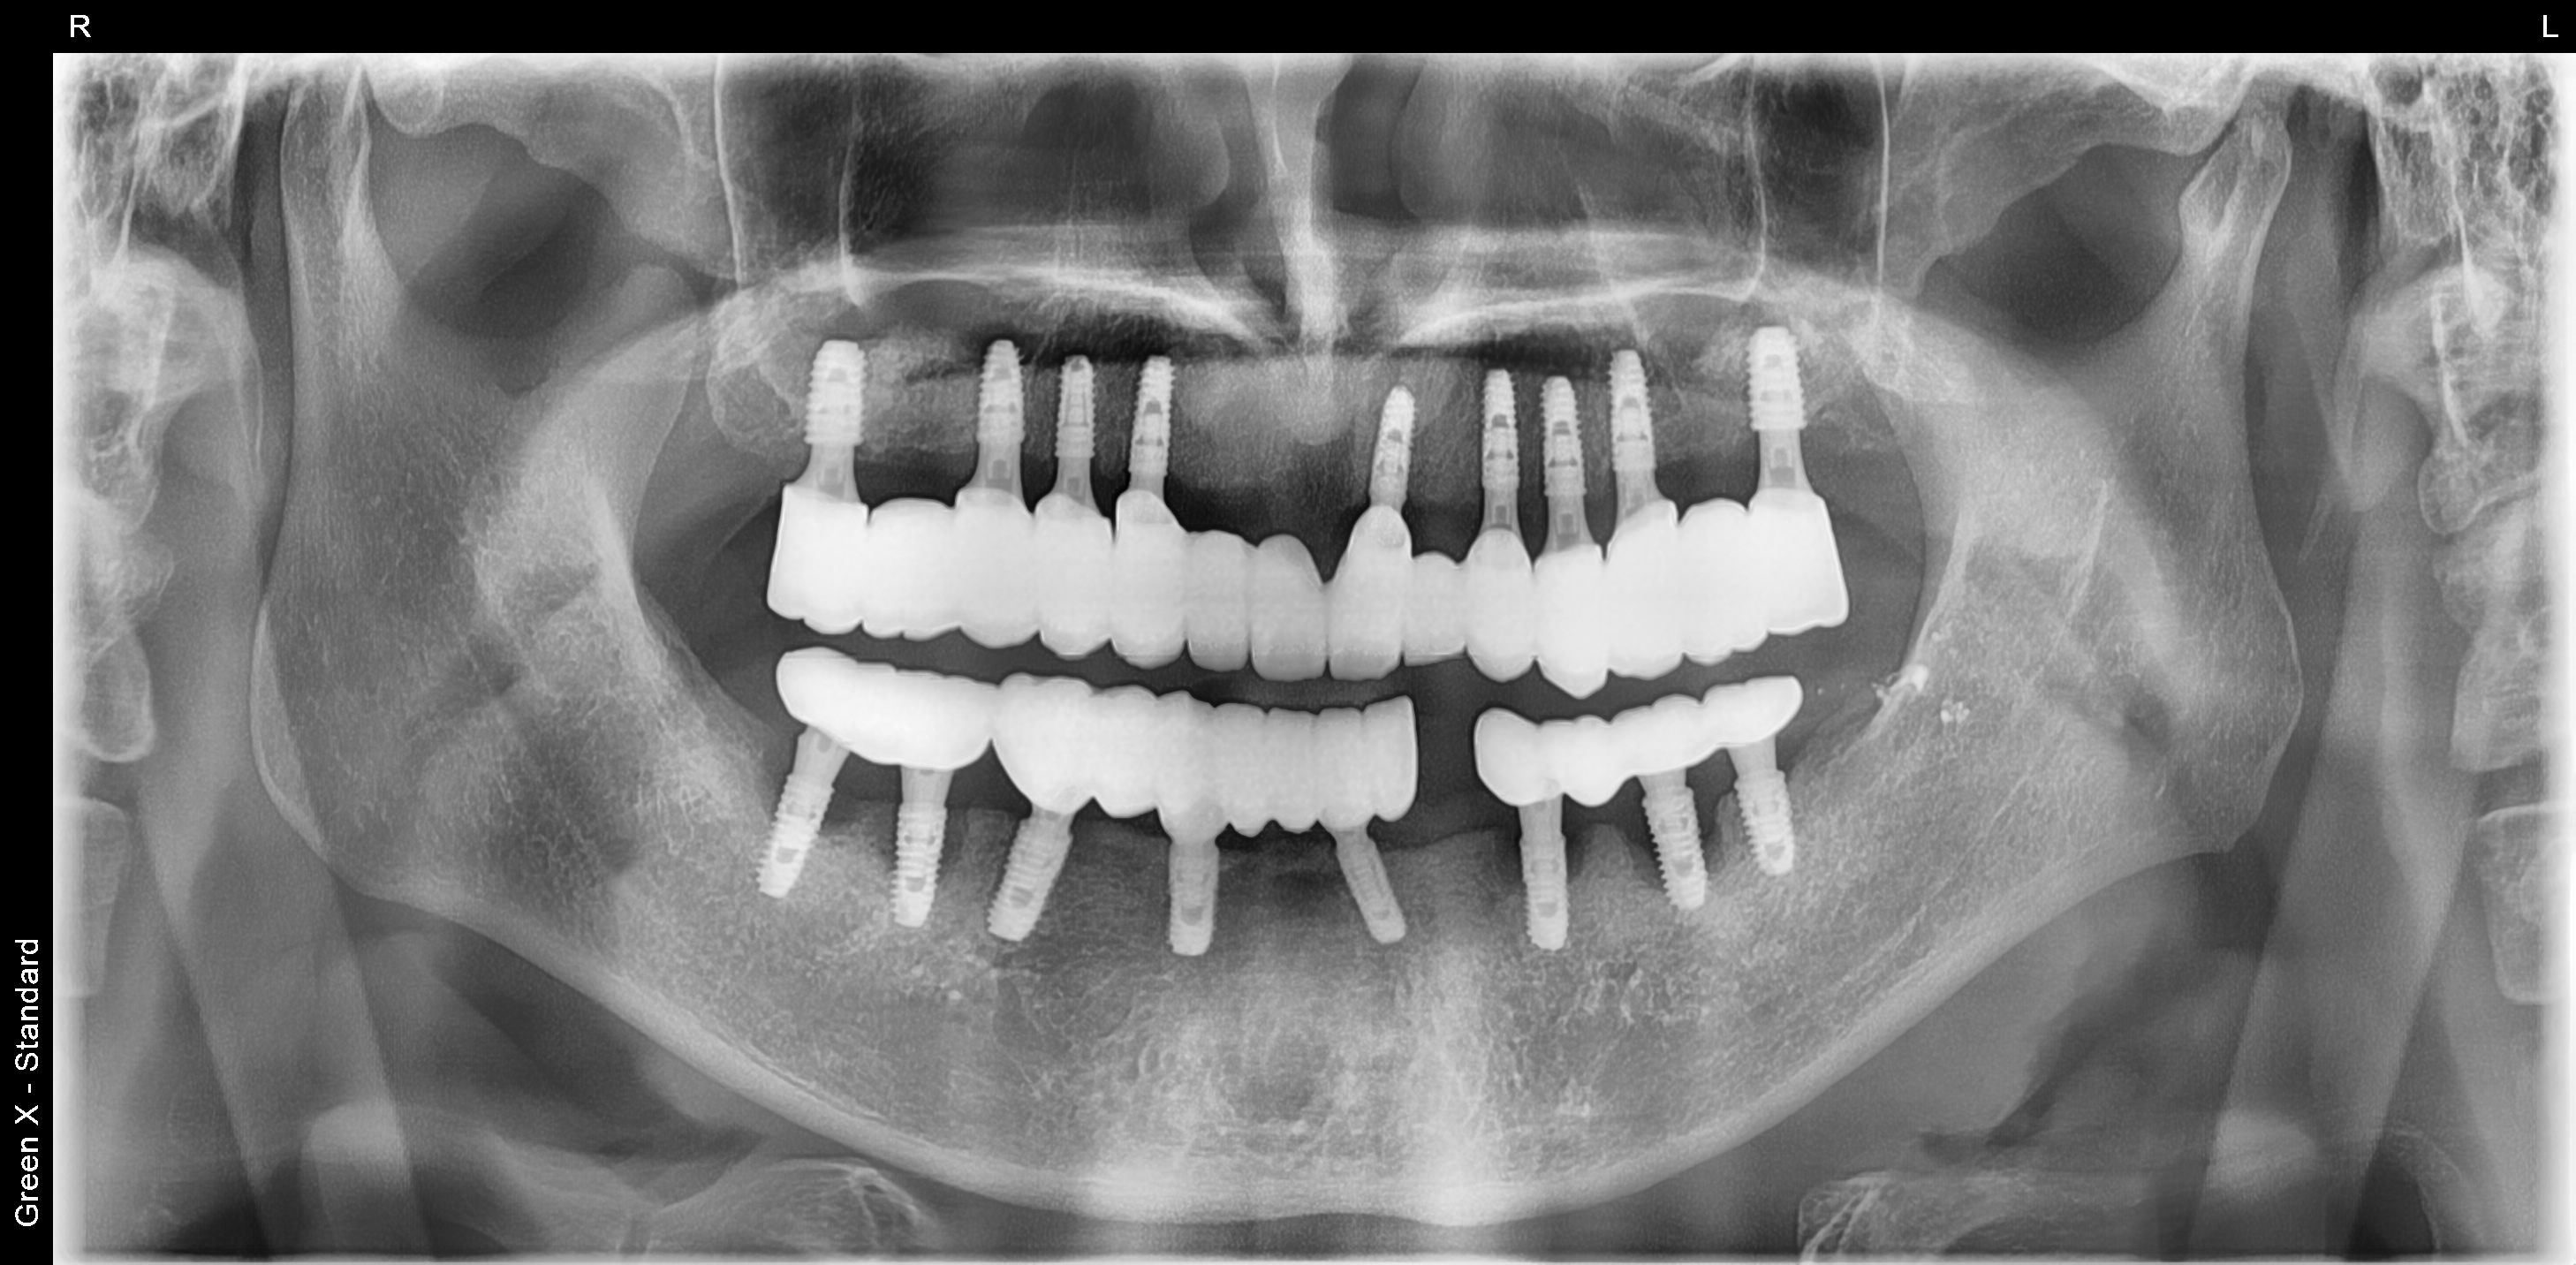

김포 풍무동 서울케이치과 위턱 전체 임플란트 사례

9개 임플란트 식립 후 고정식 보철로 위턱 전체 치아 수복한 사례입니다.

(아래턱 임플란트는 수년 전 타치과에서 식립했으나, 임플란트 주변 치조골이 소실되고 있어 추후 재식립이 필요합니다.)

<치료 전>